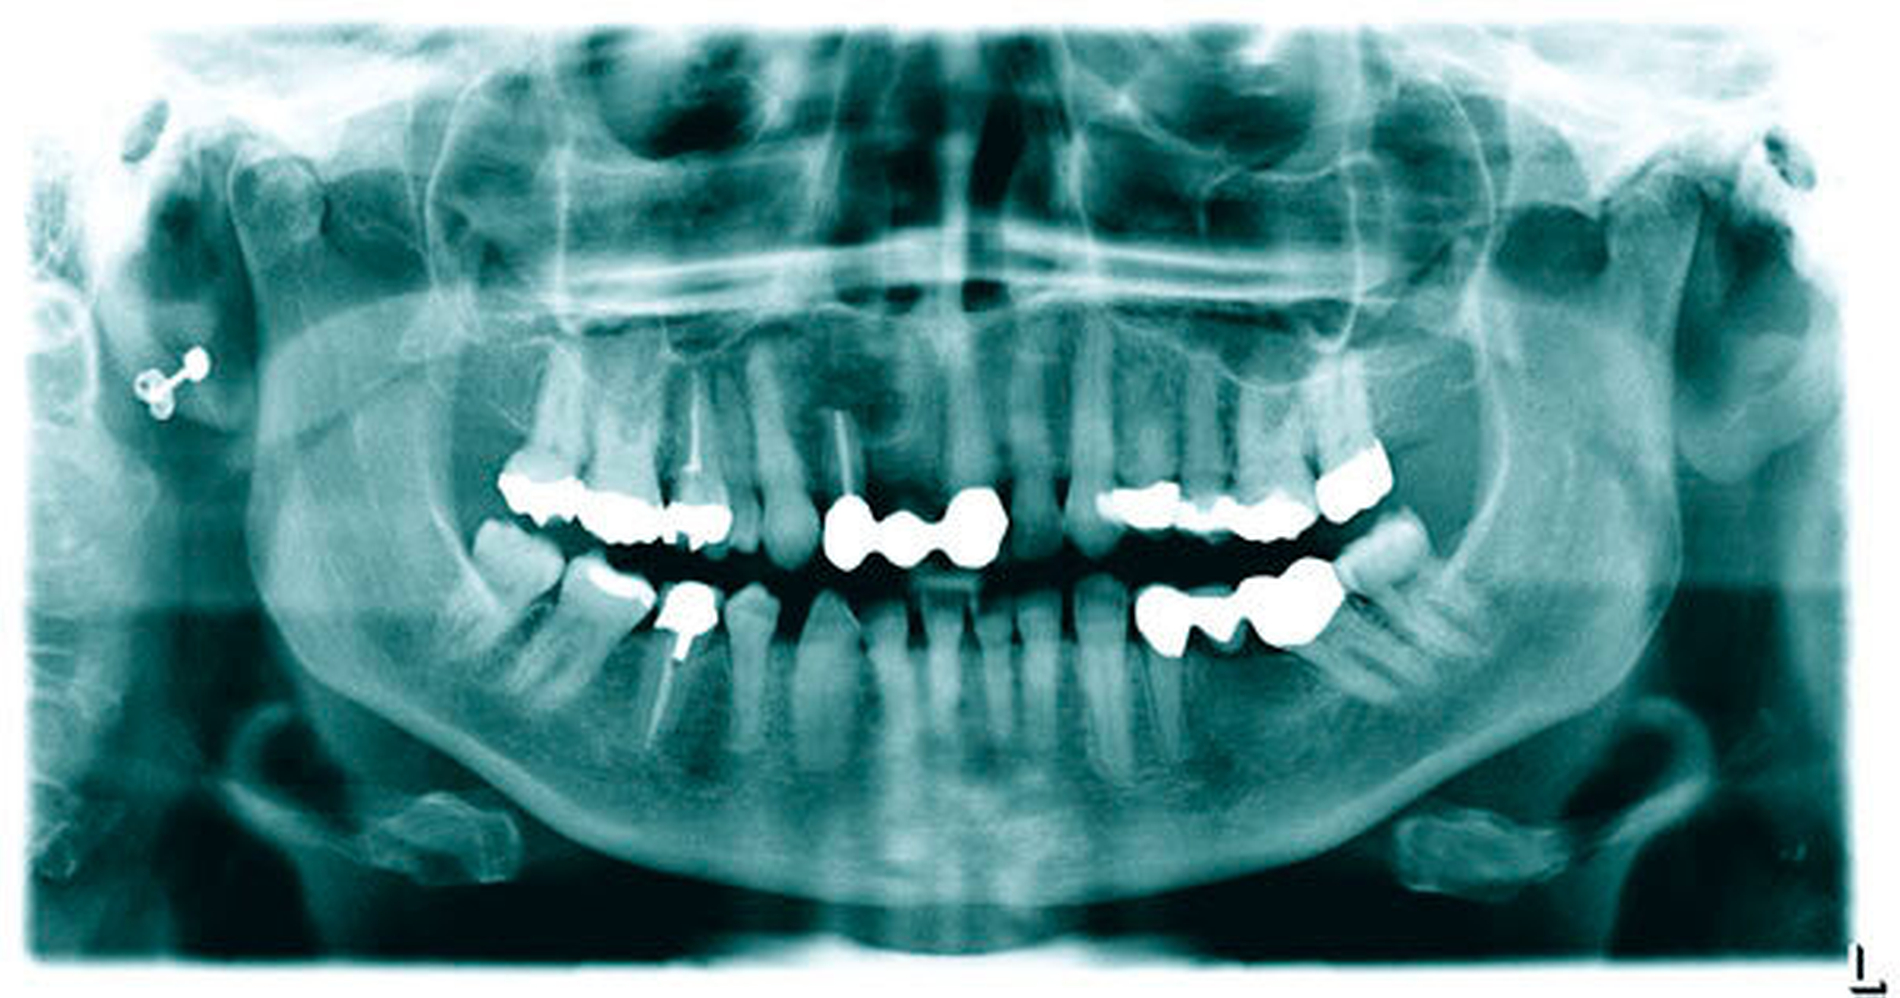

Bei der Anamnese zeigte sich klinisch freiliegender Knochen (Os librum) im Bereich des Oberkiefervestibulums Regio 11/12 mit einer Flächenausdehnung von 2 cm auf 1 cm (Abbildung 1a). Korrespondierend dazu fand sich bei der weiteren intraoralen Inspektion eine palatinale Fistel (Abbildung 1b). Bei der Patientin waren bisher weder chirurgische Eingriffe noch Bestrahlungen im Kopf-Hals-Bereich erfolgt.

Nach erfolgter Tetrazyklinmarkierung mit Doxycyclin 100 mg 1–0–0 für fünf Tage und präoperativer Abdrucknahme für eine Oberkieferverbandsplatte wurde der Eingriff in Intubationsnarkose durchgeführt. Nach marginaler Schnittführung wurden die Zähne 21, 12 und 13 entfernt sowie eine aufwendige modellierende Osteotomie im Sinne einer partiellen Resektion des Alveolarfortsatzes unter Schwarzlichtkontrolle in diesem Bereich durchgef ü hrt (Abbildung 5).

Zudem wurde eine postoperative Röntgenkontrolle mittels OPG durchgeführt (Abbildung 8). Bei optimaler Mundhygiene war der Heilungsverlauf Stadien-gerecht, ohne dass Dehiszensen oder eine Infektion aufgetreten wären.

In der Diagnostik kommt demnach neben der eingehenden oralen Inspektion der bildgebenden Untersuchung eine zentrale Bedeutung zu. Hierbei ist zu beachten, dass eine klassische konventionelle Panoramaschichtaufnahme als unzureichend gilt und – gerade auch im Sinne einer präoperativen Diagnostik – durch geeignete 3-D-Verfahren zu komplettieren ist. Außerdem wird empfohlen, eine histopathologische Aufarbeitung des Gewebes durchführen zu lassen, um zum einen maligne Prozesse ausschließen zu können und zum anderen die Diagnose zu sichern.